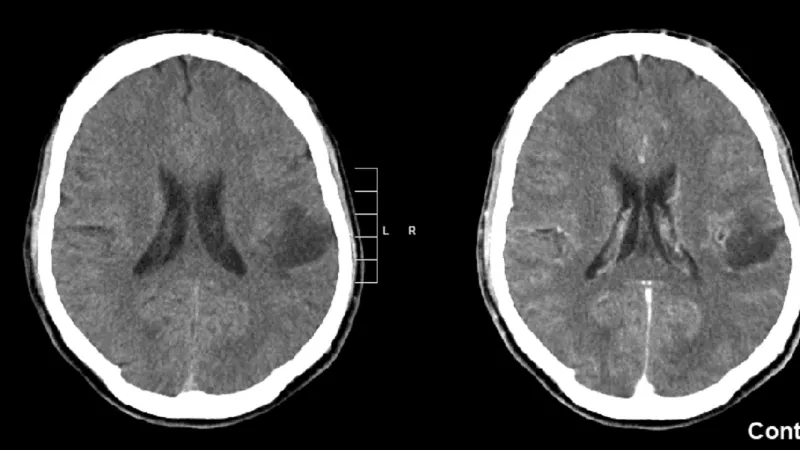

Prošli elektronické lékařské záznamy více než 20 tisíc lidí, u nichž byl diagnostikován úraz hlavy, a porovnali u nich výskyt rakoviny mozku s kontrolní skupinou, která odpovídala věku, pohlaví a socioekonomickému statusu, ale neutrpěla žádné poranění hlavy.

Zjistili, že pacienti, kteří utrpěli úraz hlavy, měli téměř čtyřikrát vyšší pravděpodobnost, že se u nich v pozdějším věku vyvine rakovina mozku, než ti, kteří úraz hlavy neměli. Autoři přitom zdůrazňují, že je důležité mít na paměti, že riziko vzniku rakoviny mozku je celkově velice nízké, takže i po úrazu zůstává pouze mírné.